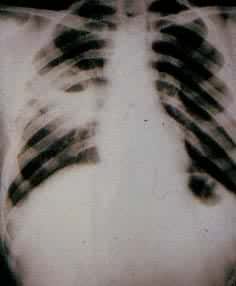

肺结核是慢性细菌性肺部感染的常见病。近年来,由于有效抗结核药物的发现和合理使用,患病率、死亡率明显下降。据国际防痨联盟资料统计,某些国家发病率仍较高,每年发现有高度传染性的病人约400万,还有400万不排菌的新结核病人。 全世界约有2000万活动性结核患者,每年有 300万人死于结核病。当前结核病仍是威胁人类健康的传染病之一。